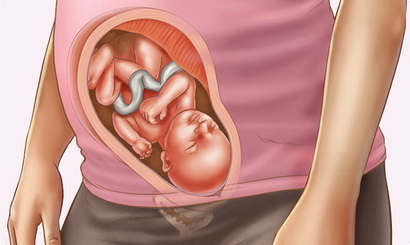

28 Тиждень вагітності розвиток плода вага і ріст

Як розташований, як лежить дитина, як часто повинен ворушитися?

Якщо ніжки вашого хлопчика знаходяться внизу - не варто турбуватися, що вам загрожує тазове передлежання плода і кесарів розтин. Він так динамічно рухається, що свого часу прийме потрібне положення. Активні ворушіння особливо помітні вночі, коли мама спить і не заколисує його своїми рухами. Вважається нормою, якщо малюк дає про себе знати раз 10 в годину, в іншому випадку проконсультуйтеся з лікарем.

На 28 тижні знімаються основні розміри малюка. норма:

- плечова кістка - 4,5 - 5,3 см,

- стегнова кістка - 4,9 - 5,7 см,

- кістки гомілки - 4,5 - 5,3 см,

- кістки передпліччя - 3,9 - 4,7 см,

- лобно-потиличний розмір - 8,3 - 9,9 см,

- окружність голівки - 24,5-28,5 см,

- окружність животиків малюків - до 28,5 см.